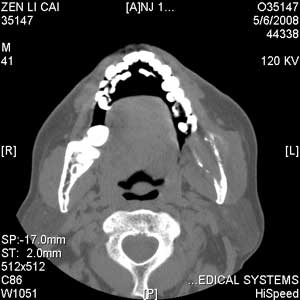

以下是引用jiangjing在2008-5-28 15:56:00的发言:[br]下颌骨左侧部骨质破坏,轻度膨胀,瘤骨形成,软组织肿胀考虑 恶性骨肿瘤-----肉瘤类